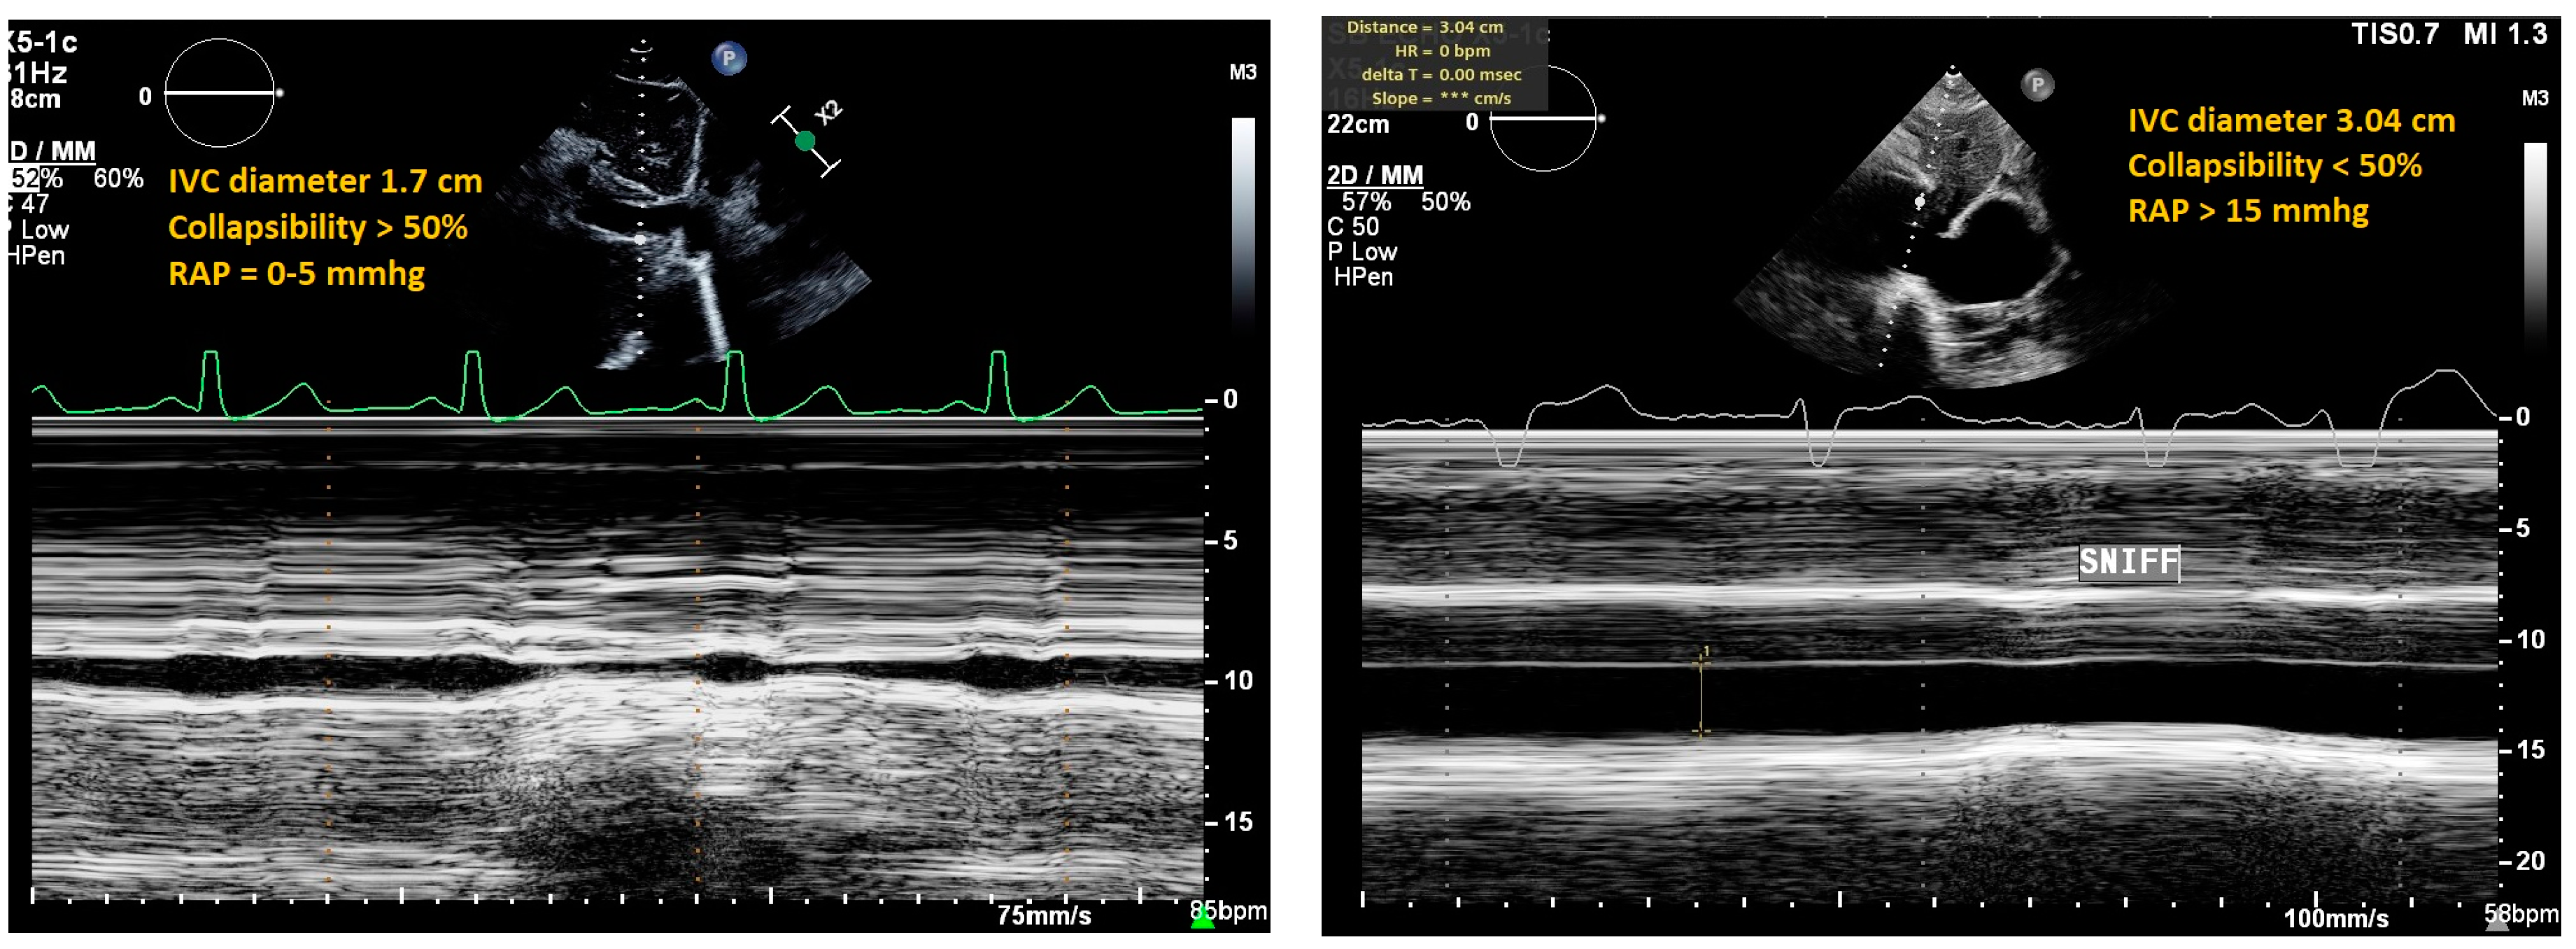

4. Inferior Vena Cava (IVC) Ultrasound

| IVC Ultrasound | ||||

| Inferior vena cava (IVC) diameter and collapsibility with inspiration | Diameter <21 mm that collapses >50% with sniff |

|

| |